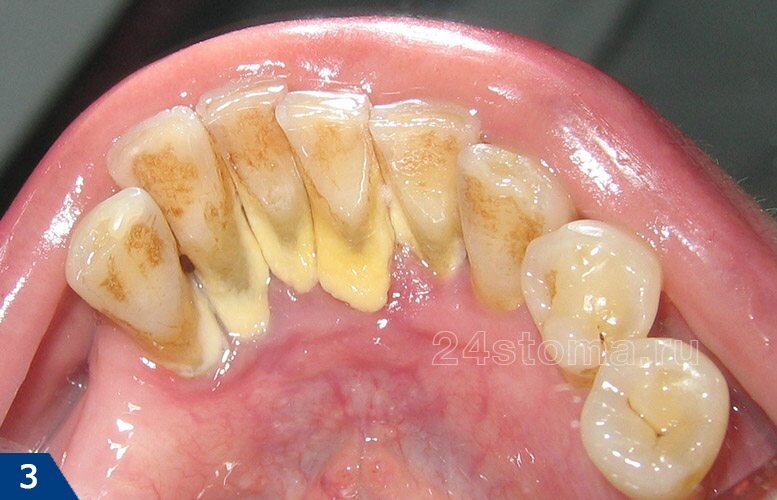

Дома, при помощи зубной щетки и пасты – можно успешно удалять с зубов только мягкий зубной налет (рис.1). Однако, если последний вовремя не счищается, то он постепенно пропитывается солями кальция, содержащимися в слюне. В результате процесса минерализации мягкий микробный налет превращается в зубной камень (рис.2-3), который можно снять только у стоматолога.

Важно: процесс первичной минерализациии мягкого зубного налета происходит в среднем за 6-12 часов. У разных людей это время может быть различным в силу особенностей, например, в составе слюны, дыхания через рот. Таким образом, если вы за это время не почистили зубы, то на зубах останется тонкий слой частично минерализованного зубного налета, который уже нельзя снять обычной зубной щеткой.

Как только на гладкой эмали зубов появляется шершавая пленка налета – процесс образования зубного камня многократно ускоряется. Это связано с тем, что к гладкой поверхности эмали зубов микроорганизмам полости рта достаточно сложно прилипнуть. К шершавой же поверхности они прилипают очень легко, очень быстро увеличивая массу зубных отложений.